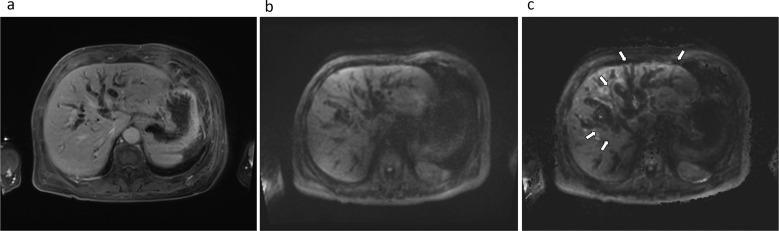

Purpose: Although diffusion-weighted imaging (DWI) with ultra-high b-values is reported to be advantageous in the detection of some tumors, its applicability is not yet known in biliary malignancy. Therefore, this study aimed to evaluate the impact of measured b = 1400 s/mm2 (M1400) and calculated b = 1400 s/mm2 (C1400) DWI on image quality and quality of lesion discernibility using a modern 3T MR system compared to conventional b = 800 s/mm2 DWI (M800).

Methods: We evaluated 56 patients who had pathologically proven biliary malignancy. All the patients underwent preoperative or baseline 3T MRI using DWI (b = 50, 400, 800, and 1400 s/mm2). The calculated DWI was obtained using a conventional DWI set (b = 50, 400, and 800). The tumor-to-bile contrast ratio (CR) and tumor SNR were compared between the different DWI images. Likert scores were given on a 5-point scale to assess the overall image quality, overall artifacts, ghost artifacts, misregistration artifacts, margin sharpness, and lesion discernibility. Repeated-measures analysis of variance with post hoc analyses was used for statistical evaluations.

Results: The CR of the tumor-to-bile was significantly higher in both M1400 and C1400 than in M800 (Pa < 0.01). SNRs were significantly higher in M800, followed by C1400 and M1400 (Pa < 0.01). Lesion discernibility was significantly improved for M1400, followed by C1400 and M800 for both readers (Pa < 0.01).

Conclusion: Using a 3T MRI, both measured and calculated DWI with an ultra-high b-value offer superior lesion discernibility for biliary malignancy compared to the conventional DWI.